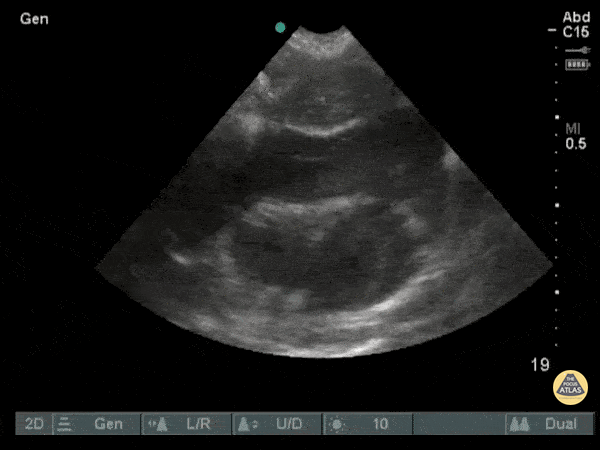

This subxiphoid view of the heart was performed on a patient after a singular stab wound to the chest. From here, we can observe a large collection of blood within the pericardial sac (hemopericardium) with visible cardiac activity still occurring. Image courtesy of Robert Jones DO, FACEP @RJonesSonoEM Director, Emergency Ultrasound; MetroHealth Medical Center; Professor, Case Western Reserve Medical School, Cleveland, OH View his original post here